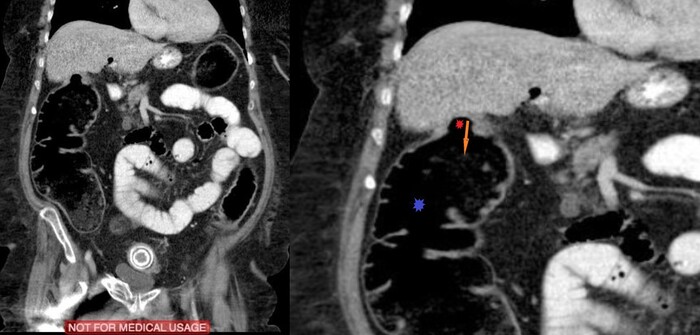

Сделали компьютерную томографию почти всего тела по протоколу множественной травмы (голова, шея, органы грудной клетки + органы брюшной полости включая позвоночник и таз).

Здесь прилагаю только КТ головы, на котором особых патологических изменеий выявлено не было: